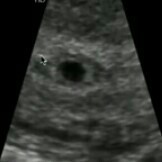

Tanong ko lang po sana kung pwede po ba yung late development na yung baby kase last menstrual ko is feb 14 tas nong 2weeks delay naku nag try naku gumamet ng hCG pero negative sya ginawa kuna every week lage negative sya nong 9weeks 3days naku sinubokan kuna ulit tas nag positive sya.. tapos nag pa check up ako yung nakita lang niya is bilog pa sya diba pag nasa 9weeks na na develop na sya yun wala pang heartbeat.